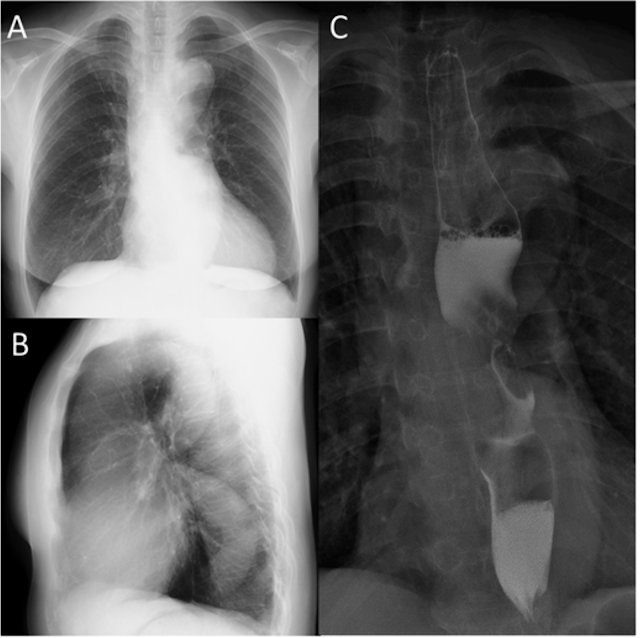

息切れで救急外来を訪れた症例

- 本例の最終診断は拡張型心筋症による非代償性左心不全